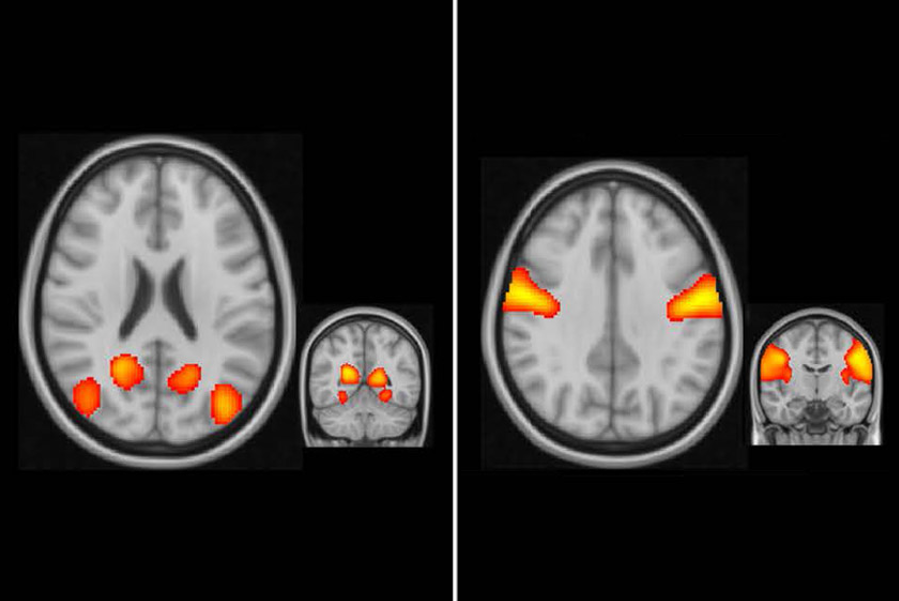

最新研究显示,自闭症孩子的大脑感觉区域连接过于紧密,这种连接阻碍了他们大脑的发育。